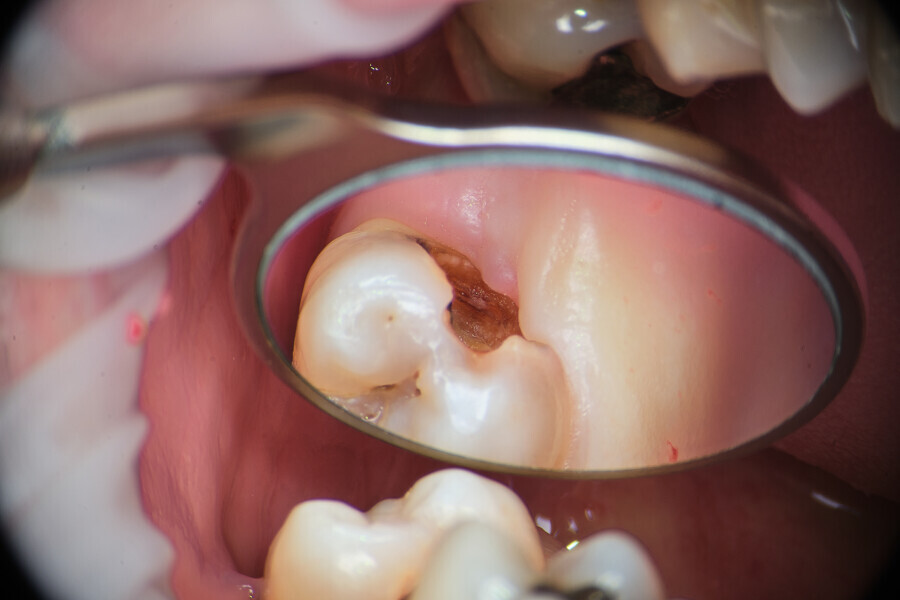

Case 1

A 43-year-old patient came to our office having been referred for endodontic treatment. During oral examination, a deep carious lesion in tooth #27 was visible. Radiographic examination confirmed the diagnosis (Fig. 6). After gingivectomy with a gingiva trimmer bur (JOTA), which was necessary in order to create space for proper isolation (Figs. 7–9), the cavity was cleaned and prepared for build-up.